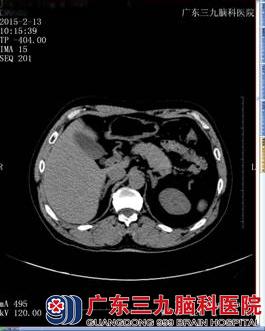

入院后2015年2月9日头颅MRI示桥脑右侧偏急性期脑梗塞灶(图一)。高血压四项示:血管紧张素I 4ng/ml,血管紧张素II 80.75pg/ml,肾素活性2.61ng/ml/h,醛固酮914.48pg/ml。离子三项示钾 3.39 ↓ mmol/L、钠 140.7 mmol/L 、氯 103.3 mmo/L。进一步完善肾上腺CT示左侧肾上腺增生(图二)。结合患者长期高血压、低血钾、醛固醇高及左侧肾上腺增生,目前高血压考虑为原发性醛固酮增多症引起的症状性高血压。诊断为:1、脑梗塞(桥脑,急性);2、高血压病(3级,极高危组)?3、原发性醛固酮增多症?给予醛固酮拮抗剂螺内酯降压,氢氯吡格雷抗血小板聚集,阿托伐他汀钙抗动脉硬化等治疗1周。血压波动大得到控制,左侧肢体无力较前明显好转。出院后患者头痛头晕缓解,肢体活动较前好转,遂回家继续治疗。

肾上腺CT+增强(图二)